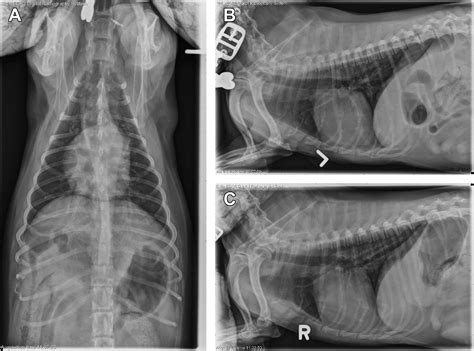

• Radiographs (X-rays): Chest X-rays can reveal inflammation, fluid, or other abnormalities in the lungs.